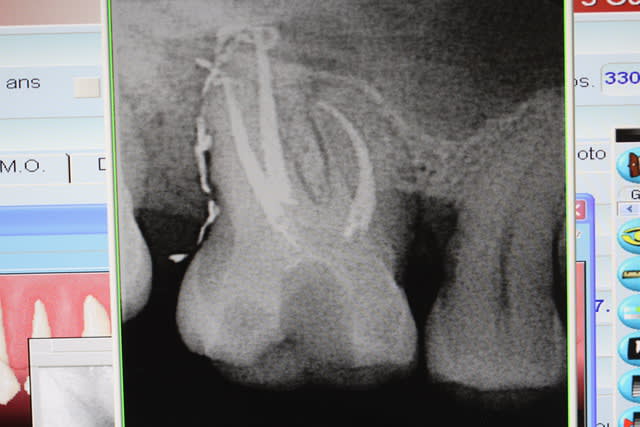

un cas réalisé depuis : une endocouronne réalisée la semaine dernière sur une nécrose d'origine paro ,

surfaçage + laser pendant la cuisson , a voir dans le temps...

C'est un joli cas mais ce n'est pas une endocouronne , c'est une couronne-endo très différent du point de vue comportement mécanique. Il aurait été possible d'être moins agressif en faisant une endo-V-Prep.